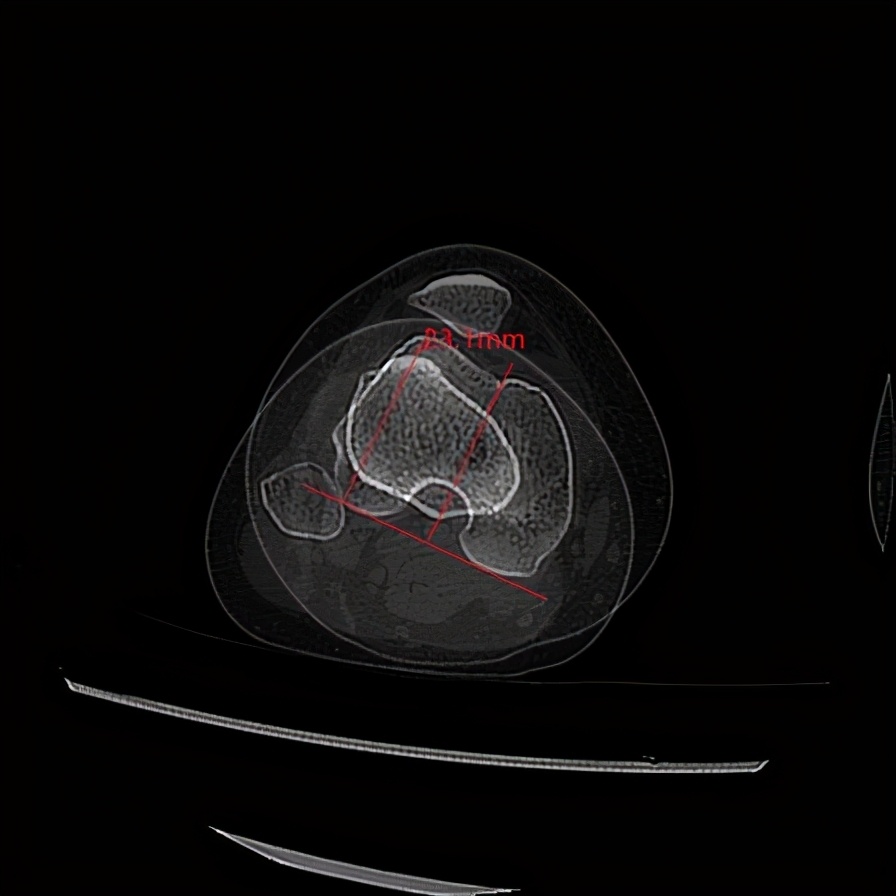

人群中CT上测量的TT-TG平均值12.7 ± 3.4 mm,而髌骨脱位患者往往在15-20mm以上。为何TT-TG会变大?其实还是因为下肢扭转畸形,股骨前倾角过大,股骨内旋,胫骨外旋导致胫骨结节和股骨滑车沟的垂线距离被拉大。来看一个实例:

图10.这位患者滑车沟仍有一定的凹度,但通过测量发现其TT-TG为23mm

上面这位患者同时还合并高位髌骨,以及B型股骨滑车发育不良。临床上很多髌骨脱位患者都像这位患者一样合并多个畸形。